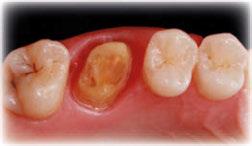

Para ilustrar el proceso, presentamos el caso de una mujer joven diagnosticada de carcinoma adenoide quístico en la región posterior del hemipaladar izquierdo (Figuras 1 y 2). El procedimiento quirúrgico realizado fue una

maxilectomía parcial que incluyó las piezas 24-26 y desde el reborde alveolar hasta la base del cráneo (Figuras 3 y 4). En este caso, la órbita y el globo ocular pudieron ser preservados. La reconstrucción inmediata se realizó mediante un colgajo de músculo temporal homolateral (Figura 5) y el defecto de la fosa temporal fue cubierto mediante una malla de titanio. Posteriormente, la paciente recibió radioterapia (Figuras 6 y 7). 2 años más tarde se diseñó un IS con anclaje en el arbotante nasomaxilar, zona subnasal izquierda

Figura 1. Imagen preoperatoria de la paciente.

Figura 2. Carcinoma adenoide quístico en región posterior del hemimaxilar izquierdo.